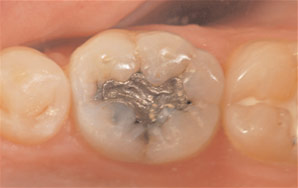

Case 1. Figure 1. Preoperative view of the patient showing recurrent decay around the existing amalgam restoration.They need and want dentistry that fits their lifestyle. As a result, dentists must be competent in providing state-of-the-art care in convenient ways to satisfy both elective and necessary treatment needs. That means they must begin to embrace same-day, in-office dentistry that enables them to take control of all-ceramic restorative processes in order to provide restorative dentistry in a whole new way

A 43-year-old male patient presented with an existing amalgam restoration in the lower left first molar that exhibited recurrent decay and fracture lines that were weakening the cusps (Case 1, Figure 1). Following a thorough examination, it was determined that the tooth required a full-coverage crown restoration. A long-time patient of record whose medical history was noncontributory, he was a busy agent for the Federal Bureau of Investigation who was “devastated” at the prospect of undergoing dental procedures for a crown.